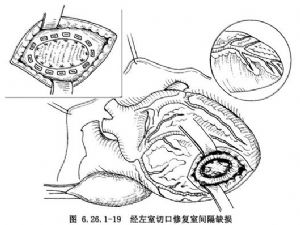

(3)修補缺損:此類缺損均需應用補片修補,假如爲多個缺損,而且彼此都很鄰近,亦可應用1塊大補片覆蓋於全部缺損上,應用帶小墊片4-0無創縫線做間斷褥式縫合(圖6.26.1-19)。